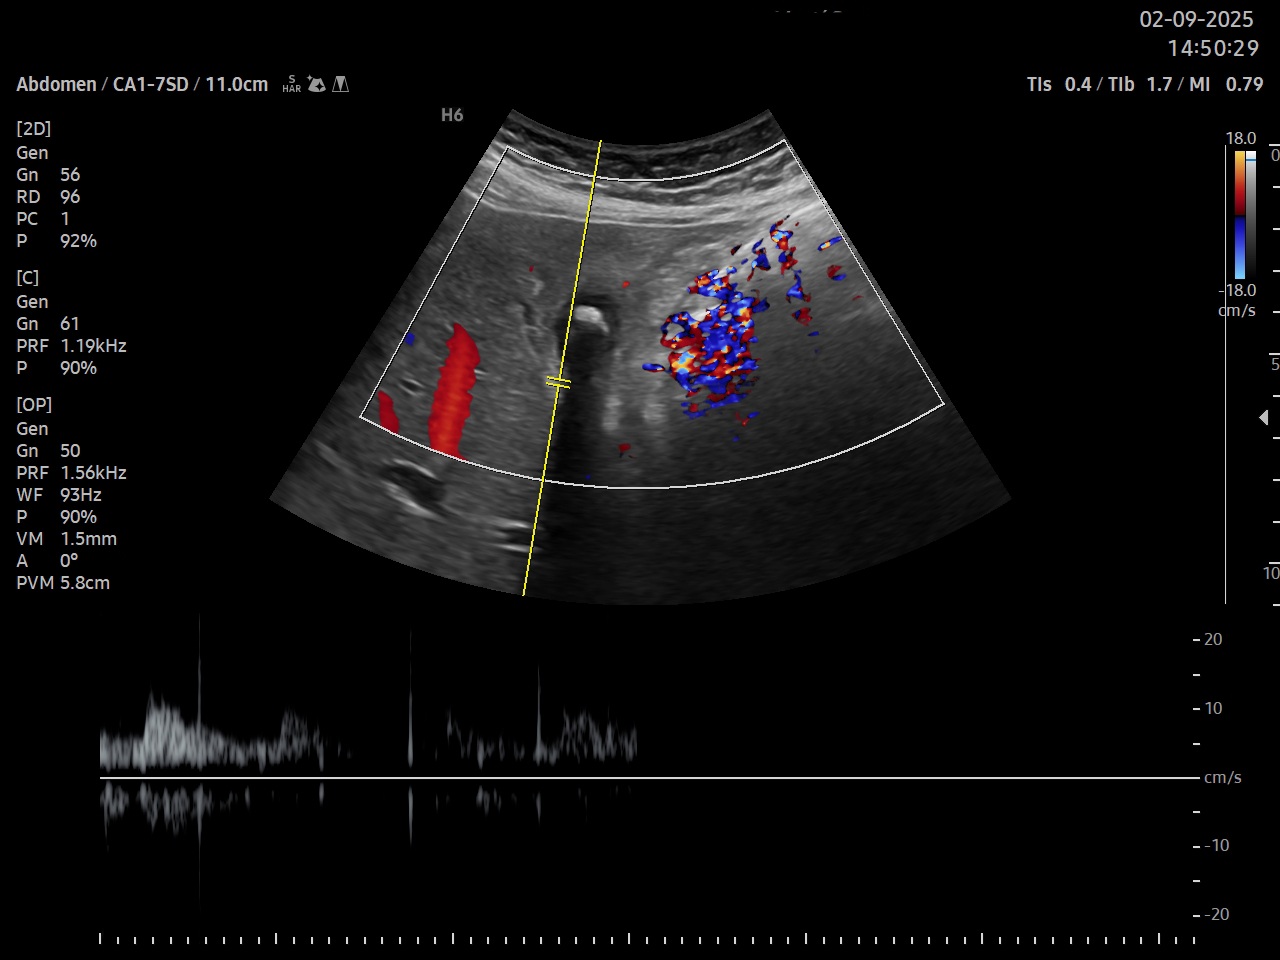

Ecografía clínica: parénquima hepático homogéneo de bordes lisos, signo de Murphy ecográfico positivo, vesícula biliar distendida a pesar de no ayuno con tres imágenes hiperecogénicas con centelleo y sombra posterior, pared engrosada hiperecogénica, se detecta líquido perivesicular. Doppler pulsado a nivel de arteria cística. Páncreas visible en parte sin alteraciones en su interior, no se visualiza Wirsung ni dilatación a nivel de ampolla de Vater, bazo y riñones de tamaño y ecoestructura normal, mioma uterino, vejiga parcialmente replecionada, aorta de calibre normal.

Según los criterios de Tokio 2018, el diagnóstico de colecistitis se establece con la combinación de signos locales de inflamación: dolor en hipocondrio derecho y Murphy positivo, signos sistémicos de inflamación: leucocitosis con neutrofilia, hallazgos de imagen: pared vesicular engrosada (mas de 3 mm), vesícula distendida, presencia de litiasis y Murphy ecográfico positivo, líquido pericístico así como elevación de la velocidad pico sistólica en la arteria cística.